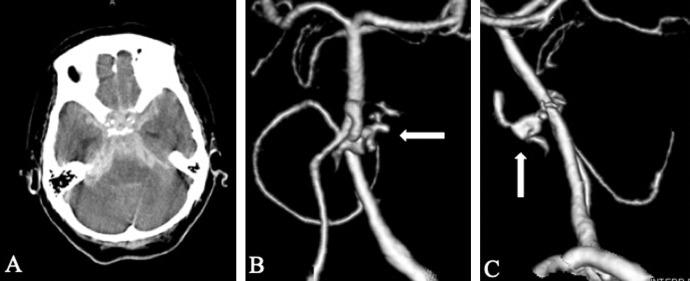

Dissecting aneurysms of the anterior inferior cerebellar artery (AICA) are rare. Few reports suggested that coil embolization and parent artery occlusion (PAO) would be valuable treatment options against dissecting AICA aneurysms. We report a case of PAO against dissecting aneurysm involving the proximal AICA and discuss the therapeutics and literature review of this pathology. A 69-year-old woman was referred to our hospital, and neurological examination revealed a semicoma (Hunt and Hess grade IV). Brain computed tomography (CT) established the diagnosis of Fisher group 3 subarachnoid hemorrhage (SAH), CT angiography revealed an extravasation near the clivus, while digital subtraction angiography showed no signs of dissection. Conservative treatment was administered, and repeated angiography on day 13 showed a pseudoaneurysm and false lumen in the left proximal AICA. The patient was in poor health condition, and endovascular therapy (EVT) of the left AICA was performed to minimize invasion. The PAO was successful with no severe ischemic damage to the brainstem and cerebellum. However, the general condition gradually deteriorated, and the patient expired on day 24. Since open surgery for dissecting AICA aneurysm is technically challenging and revascularization procedure is often required, the rapidly developing EVT is a viable alternative. Although preservation of the proximal AICA is usually necessary, PAO without revascularization procedure was performed to avoid the high risk of regrowth and re-rupture of the dissecting aneurysm with respect to the patient's poor health condition. Hence, EVT is a viable option when microsurgery is contraindicated for treating dissecting AICA aneurysms.

小脑前下动脉(AICA)夹层动脉瘤较为罕见。少数报告表明,弹簧圈栓塞和载瘤动脉闭塞(PAO)是治疗AICA夹层动脉瘤的有效选择。我们报告一例针对累及AICA近端的夹层动脉瘤进行PAO的病例,并讨论该病理情况的治疗方法及文献综述。一名69岁女性被转诊至我院,神经系统检查显示为半昏迷状态(Hunt和Hess分级IV级)。脑部计算机断层扫描(CT)确诊为Fisher 3级蛛网膜下腔出血(SAH),CT血管造影显示斜坡附近有造影剂外渗,而数字减影血管造影未显示夹层迹象。给予保守治疗,第13天重复血管造影显示左侧AICA近端有假性动脉瘤和假腔。患者健康状况较差,为尽量减少侵袭,对左侧AICA进行了血管内治疗(EVT)。PAO成功实施,未对脑干和小脑造成严重缺血性损害。然而,患者总体状况逐渐恶化,于第24天死亡。由于AICA夹层动脉瘤的开放手术在技术上具有挑战性且通常需要进行血管重建手术,快速发展的EVT是一种可行的替代方案。尽管通常需要保留AICA近端,但考虑到患者健康状况较差,为避免夹层动脉瘤再生长和再破裂的高风险,在未进行血管重建手术的情况下进行了PAO。因此,当显微手术禁忌用于治疗AICA夹层动脉瘤时,EVT是一种可行的选择。